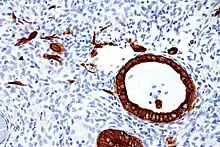

Cytokeratins are keratin proteins found in the intracytoplasmic cytoskeleton of epithelial tissue. They are an important component of intermediate filaments, which help cells resist mechanical stress.[1] Expression of these cytokeratins within epithelial cells is largely specific to particular organs or tissues. Thus they are used clinically to identify the cell of origin of various human tumors.

Expression of these cytokeratins is largely organ or tissue specific. The subsets of cytokeratins which an epithelial cell expresses depends mainly on the type of epithelium, the moment in the course of terminal differentiation and the stage of development. Thus a specific cytokeratin expression profile allows the identification of epithelial cells. Furthermore, this applies also to the malignant counterparts of the epithelia, (carcinomas), as the cytokeratin profile is generally retained. Thus the study of cytokeratin expression by immunohistochemistry techniques is a tool of immense value widely used for tumor diagnosis and characterization in surgical pathology.[5]